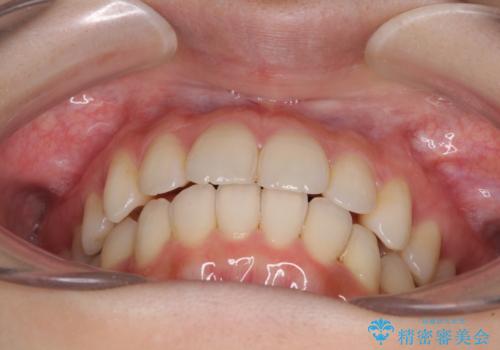

- 前歯のデコボコを気にして来院された患者様です。

叢生と捻転が随所に認められるものの、マウスピースで十分対応可能であったため、インビザラインにて矯正治療を行うこととしました。

マウスピース矯正は毎日しっかりと装着することがとても大切です。

こちらの方はしっかりと指示を守って装着してくださったため、予定通り治療を終えることができました。